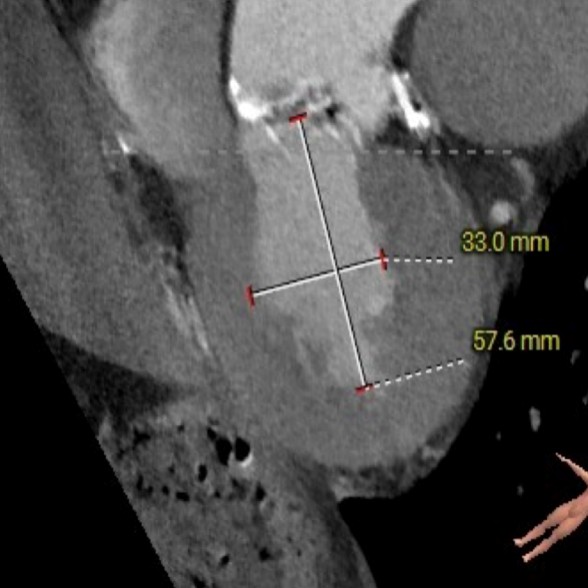

冠脉高度测量

LEFT CORONARY

左冠开口高度20.4mm

RIGHT CORONARY

右冠开口高18.8mm